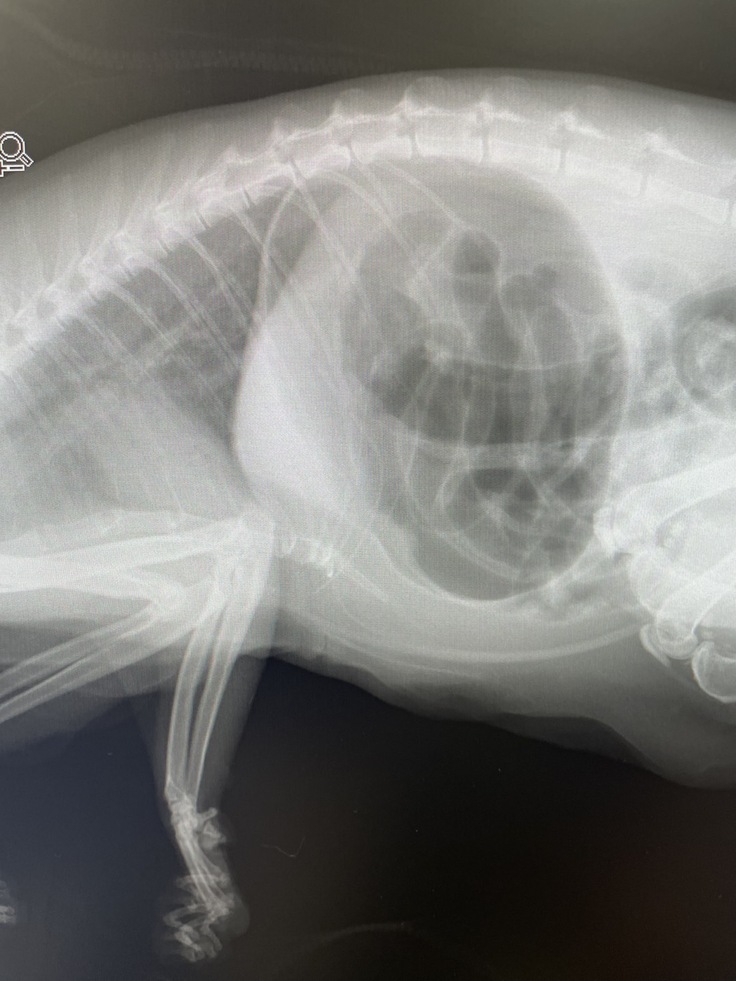

ひみこちゃんは最近お腹の張りと、苦しそうな様子がありました。

便秘かなと思ったんですが、レントゲン検査で、ガスが溜まり胃拡張になっていることがわかりました。

内服治療がすぐに効いて翌日にはお腹のふくらみもなくなり、投薬は続けていましたが、またガスでお腹が張ってきて苦しそうな様子です。

胃拡張は猫ではめずらしく、胃捻転している可能性やその他の異常があるかもしれませんが、明日、また別のかかりつけ医へ行ってきます。